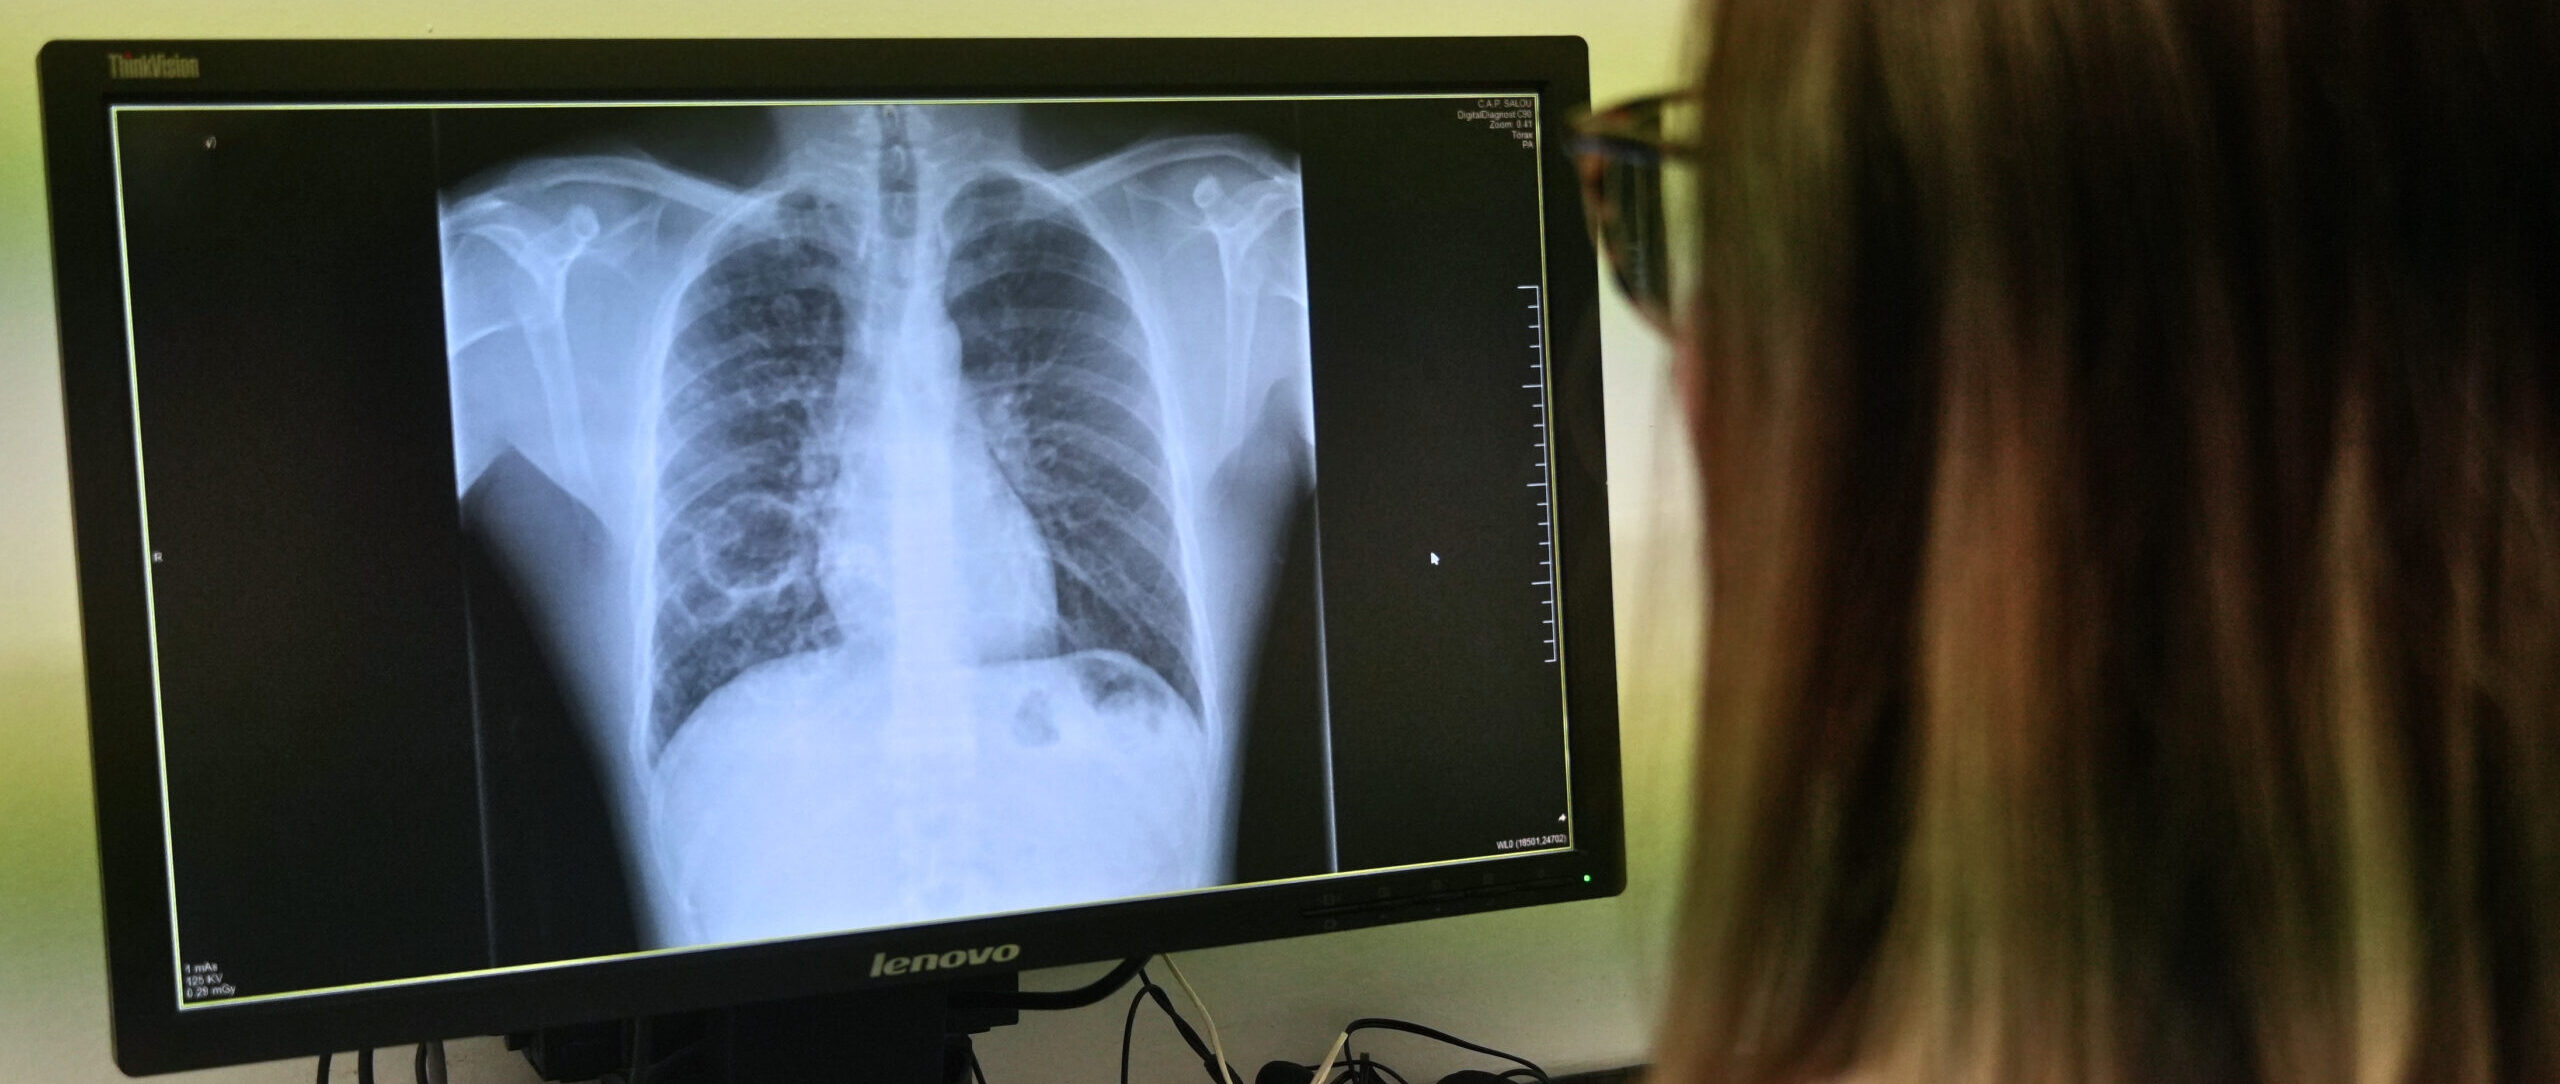

La tuberculosis afecta principalmente al pulmón, aunque también puede tener una afectación extrapulmonar. Solo las personas con afectación pulmonar activa son transmisibles, ya que es en el pulmón donde la bacteria se multiplica en gran cantidad y puede expulsarse al aire.